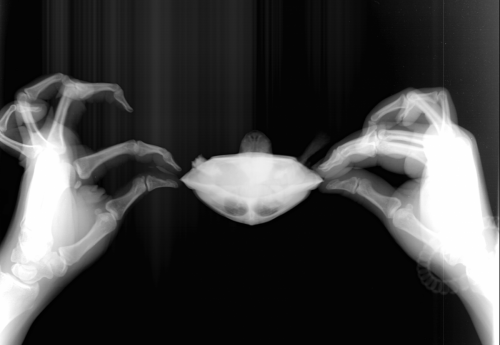

Юля48 Ваше имя: Юля Локация: Липецк Опубликовано: 25 июля 2019 Автор Опубликовано: 25 июля 2019 @moth добрый день! сделали рентген. Не знаю , так или нет. У нас только в одном месте его делают. Врач на нас как на инопланетян смотрел с черепахой . первый снимок вобще ничего не понятно(((

Консультанты moth Ваше имя: Мария Локация: Москва Опубликовано: 25 июля 2019 Консультанты Опубликовано: 25 июля 2019 @Юля48 я обработала немного снимки для четкости, выложите их в группу. Там точно по-моему газы есть и ещё что-то непонятное, нужно чтобы Артём посмотрел.

Юля48 Ваше имя: Юля Локация: Липецк Опубликовано: 26 июля 2019 Автор Опубликовано: 26 июля 2019 (изменено) @moth Добрый день! ответил врач по снимкам. "есть признаки, как вздутие жкт, так и пневмонии. Я бы начал курс инъекций антибиотика (байтрил, марфлоксин). Так же внутрь задать несколько раз эспумизан суспензию. Но это сложная процедура. Елец, это липецкая область. При возможности, стоит добраться до врачей в Липецке или Тамбове, занимающихся лечением рептилий, для оценки состояния черепахи" Не подскажете в какое место точно колоть антибиотик? шприц самый маленький нужен ? И если эспумизан давать , то как? Изменено 26 июля 2019 пользователем Юля48

Юля48 Ваше имя: Юля Локация: Липецк Опубликовано: 22 августа 2019 Автор Опубликовано: 22 августа 2019 (изменено) @moth Добрый день! Мария,Мы повторили рентген . Отправила в группу , но пока ждем ответа , может вы что-то подскажете. Врач на рентгене сказал что легкие хорошие, антибиотик помог (Кололи Байтрил почти месяц как сказал Артем) .Но у нас еще другая проблема . Пневматоз кишечника. На снимке явно видно большие каловые массы и вздутие. Как можно помочь с туалетом ему? общее состояние без изменений. Не ест, не какает, лапы задние для передвижения не использует, плавает по дну. Разве что , немного меньше стал раздувать шею. Изменено 22 августа 2019 пользователем Юля48